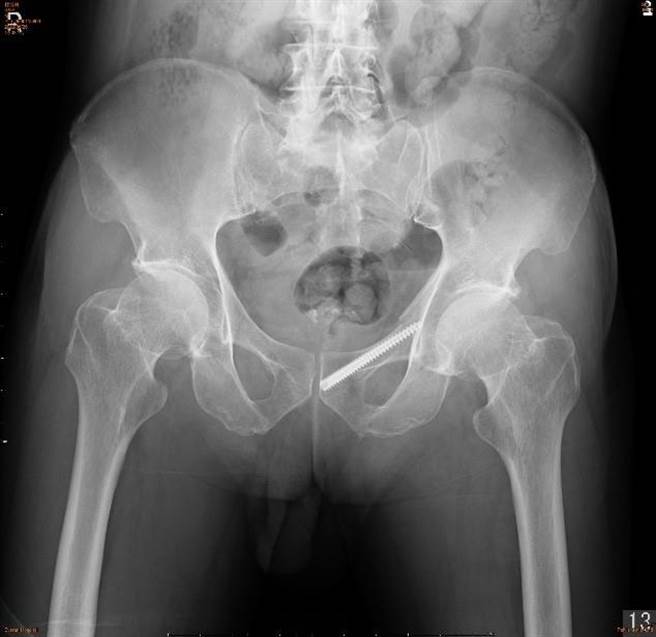

微創骨盆手術僅以1公分左右的傷口,即可將鋼釘固定至骨折位置,可大幅減少術後病人復原時間。(長安醫院提供/潘虹恩台中傳真)

據了解,75歲林男長期患有骨質疏鬆症不自知,因意外從椅子跌坐下來後,發現竟無法動彈,家人緊急送至長安醫院,經檢查發現,左邊骨盆的恥骨上支及恥骨下支兩處骨折。與家人討論後決定接受「微創骨盆手術」,透過僅1公分左右的傷口將鋼釘固定至骨折位置。

趙子鎔說明,此手術是利用透視床和X光機,以1公分左右的傷口將鋼釘固定至骨折位置,雖然手術過程較繁瑣,但術後病人可大幅減少復原時間,也可降低傷口照護的風險;趙子鎔說,術後晚上,林男已可自由地在床上翻身,疼痛指數只剩1~2分,隔日已可輕鬆地起身下床,回診追蹤也表示移動自如,漸漸恢復以往的活動力。